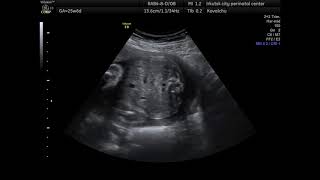

Случай правосторонней диафрагмальной грыжи

Диафрагмальная грыжа

Диафрагмальная грыжа – аномалия развития, характеризующийся наличием врожденного дефект диафрагмы, через который, во внутриутробном ...